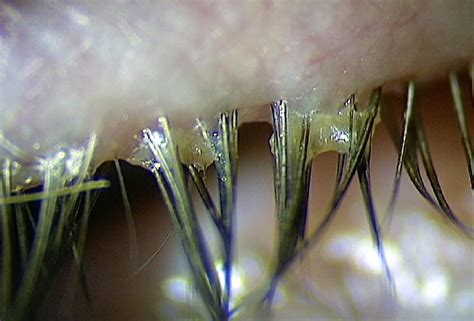

Zylindrische Schuppenbildung vom Wimpern-Haarbalg kommend

Die Hauptsymptome sind Juckreiz, Brennen, Fremdkörpergefühl, Krustenbildung und Rötung des Lidrandes sowie verschwommenes Sehen. Zu den Symptomen gehören zylindrische Schuppen, Ausfall von Augenwimpern, Entzündung des Augenlidrandes, Meibom-Drüsen-Dysfunktion (Funktionsstörung), Blepharo Konjunktivitis (Entzündung der Bindehaut am Lidrand) und Blepharo Keratitis (Entzündung der Hornhaut).

2. Spaltlampenuntersuchung: typische zylindrische Schuppen an der Wurzel der Wimpern.

Demodex-Milben, insbesondere folliculorum, konsumieren Epithelzellen am Haarfollikel, was zu einer Follikelausdehnung führt, die zur Bildung lockerer oder falsch gerichteter Wimpern beitragen kann. Mikroabschürfungen, die durch die Milbenkrallen verursacht werden, können eine epitheliale Hyperplasie (übermäßige Zellbildung, deutsch, english ) und eine reaktive Hyperkeratinisierung (Hornzellenbildung) um die Basis der Wimpern hervorrufen und zylindrische Schuppen bilden. D. brevis kann die Öffnungen der Meibom-Drüsen verstopfen, was zu einer Störung der Meibom-Drüse mit Lipidrissmangel (schlechte Tränenfilmqualität) führt. D. Brevis bohrt sich in der Regel tief in die Meibom-Drüsen, und sein chitinöses Exoskelett ist ein Fremdkörper, der granulomatöse (Knötchen, bildende) Reaktionen hervorruft. Brevis wurde im Zentrum von Meibom-Granulomen beobachtet, umgeben von Epithelzellen, Histiozyt-Fibroblasten link, Lymphozyten und Plasmazellen. Somit können Demodex-Milben eine potenzielle Ursache für wiederkehrende und unbehandelbare (refraktär) Chalazion (Hagelkorn-Entzündung) sein. Das Gerstenkorn (Hordeolum) ist eine Entzündung der Talgdrüse im Lidrand und Augenwinkeln.